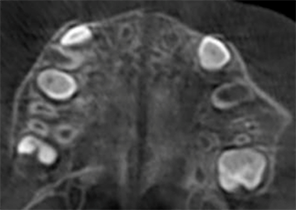

Điều trị an toàn và hiệu quả lâm sàng1: Điều trị nong hàm khẩu cái Invisalign giúp mở rộng đường khớp giữa vòm miệng.4

Phương pháp điều trị nong hàm khẩu cái Invisalign giúp bạn đạt được mục tiêu lâm sàng là mở rộng đường khớp giữa vòm miệng3.

Hệ thống nong hàm khẩu cái Invisalign được chỉ định để điều trị chỉnh nha cho các ca sai khớp cắn. Hệ thống được sử dụng để nong nhanh và sau đó giữ cung xương và/hoặc cung răng hàm trên hẹp (hàm trên, cung răng và răng, khẩu cái) với răng sữa, răng hỗn hợp hoặc răng vĩnh viễn trong quá trình điều trị chỉnh nha hoặc chỉnh hình ở trẻ em hoặc thanh thiếu niên. Tham khảo Hướng dẫn sử dụng Hệ thống nong hàm khẩu cái Invisalign để biết danh sách đầy đủ các chống chỉ định, cảnh báo và biện pháp phòng ngừa của thiết bị.